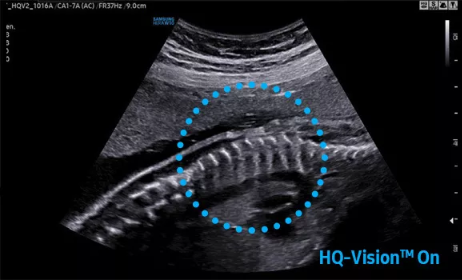

2D成像方面,Hera i10集成了包括ShadowHDR?、HQ-Vision?、ClearVision等多項具有三星“血統(tǒng)”的技術,加強了圖像的陰影抑制、減少偽影、緩和模糊區(qū)。